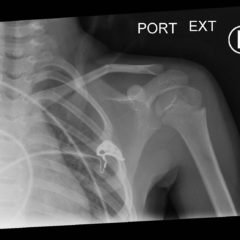

Infant Clavicle Fracture

Infant clavicle fracture, trauma, MVC, motor vehicle collision

Photograph

Pediatric Clavicle Fracture